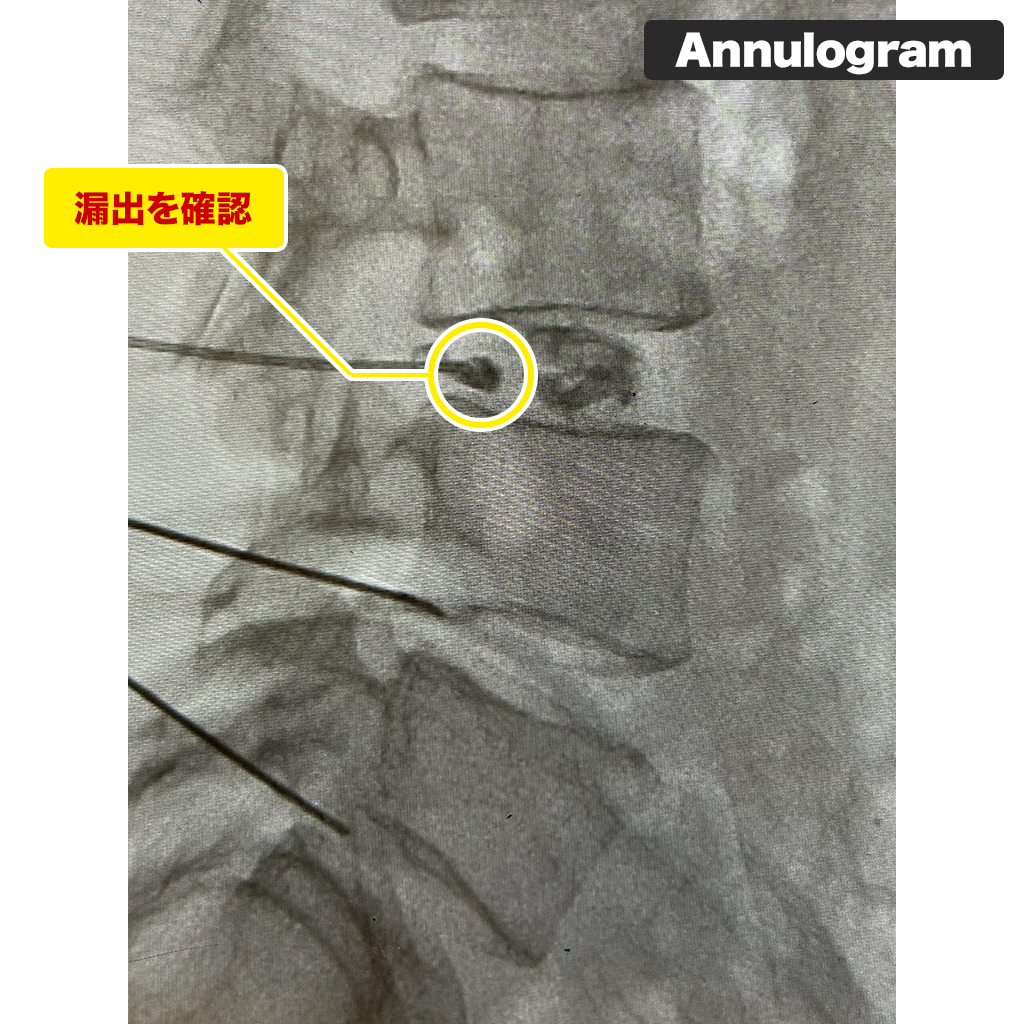

Annulogram検査

L4/5でHIZに一致した部位のリークを認めます。巨大な線維輪の損傷部位です。

L3/4は椎間板の変性をほぼ認めませんが、造影検査をすると小さいですが損傷を認めました。早期の損傷が見つかりましたが、検査を行わないとわからかなったことです。「見た目はきれいだから大丈夫だろう」で済まさず、プロトコル通りにすることが重要だと改めて思いました。襟を正し、粛々とやるべきことをやることが重要なのですね。